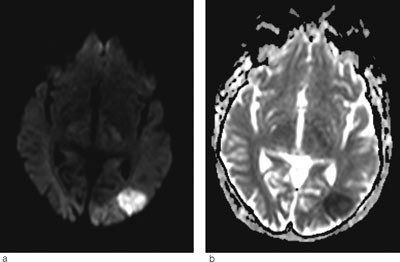

Hjerneødem kan være cytotoksisk (cellulært) eller vasogent (interstitielt). Ofte foreligger det en kombinasjon. Ved hjerneinfarkt dominerer det cytotoksiske ødemet og celledød (fig 3a-b). Ved posterior reversibel encefalopati-syndrom får man et vasogent ødem som i utgangspunktet er reversibelt, men som uten behandling kan utvikles til cytotoksisk ødem og gi permanent cellulær skade. Ved hjelp av MR med diffusjonsvekting (DWI) og ADC-kart kan man skille mellom cytotoksisk og vasogent ødem. Ved MR med diffusjonsvekting er det høyt signal ved cytotoksisk ødem, mens det vanligvis er lavt signal eller ingen signalendringer ved vasogent ødem. I noen tilfeller får man likevel høyt signal ved posterior reversibel encefalopati-syndrom. Dette skyldes at DWI-resultatet er satt sammen av bidrag fra både T2-vekting og diffusjonsvekting. Høyt signal på T2 kan derfor skinne igjennom til diffusjonsbildet. Dette var også tilfellet hos vår pasient (fig 1c). Det er derfor viktig med ADC-kart, hvor bidraget fra T2 er fjernet og man får et rent diffusjonsbilde (7). ADC-kart viser alltid lavt signal ved cytotoksisk ødem og høyt signal ved vasogent ødem, som ved posterior reversibel encefalopati-syndrom (fig 1d).

Klinisk vil man ofte få mistanke om hjerneslag fra bakre kretsløps forsyningsområde. Dette kan utelukkes ved MR-undersøkelse, som tidligere beskrevet. Dersom MR cerebrum viser vasogent ødem, må også andre mulige årsaker enn de som er kjent å kunne utløse posterior reversibel encefalopati-syndrom vurderes.